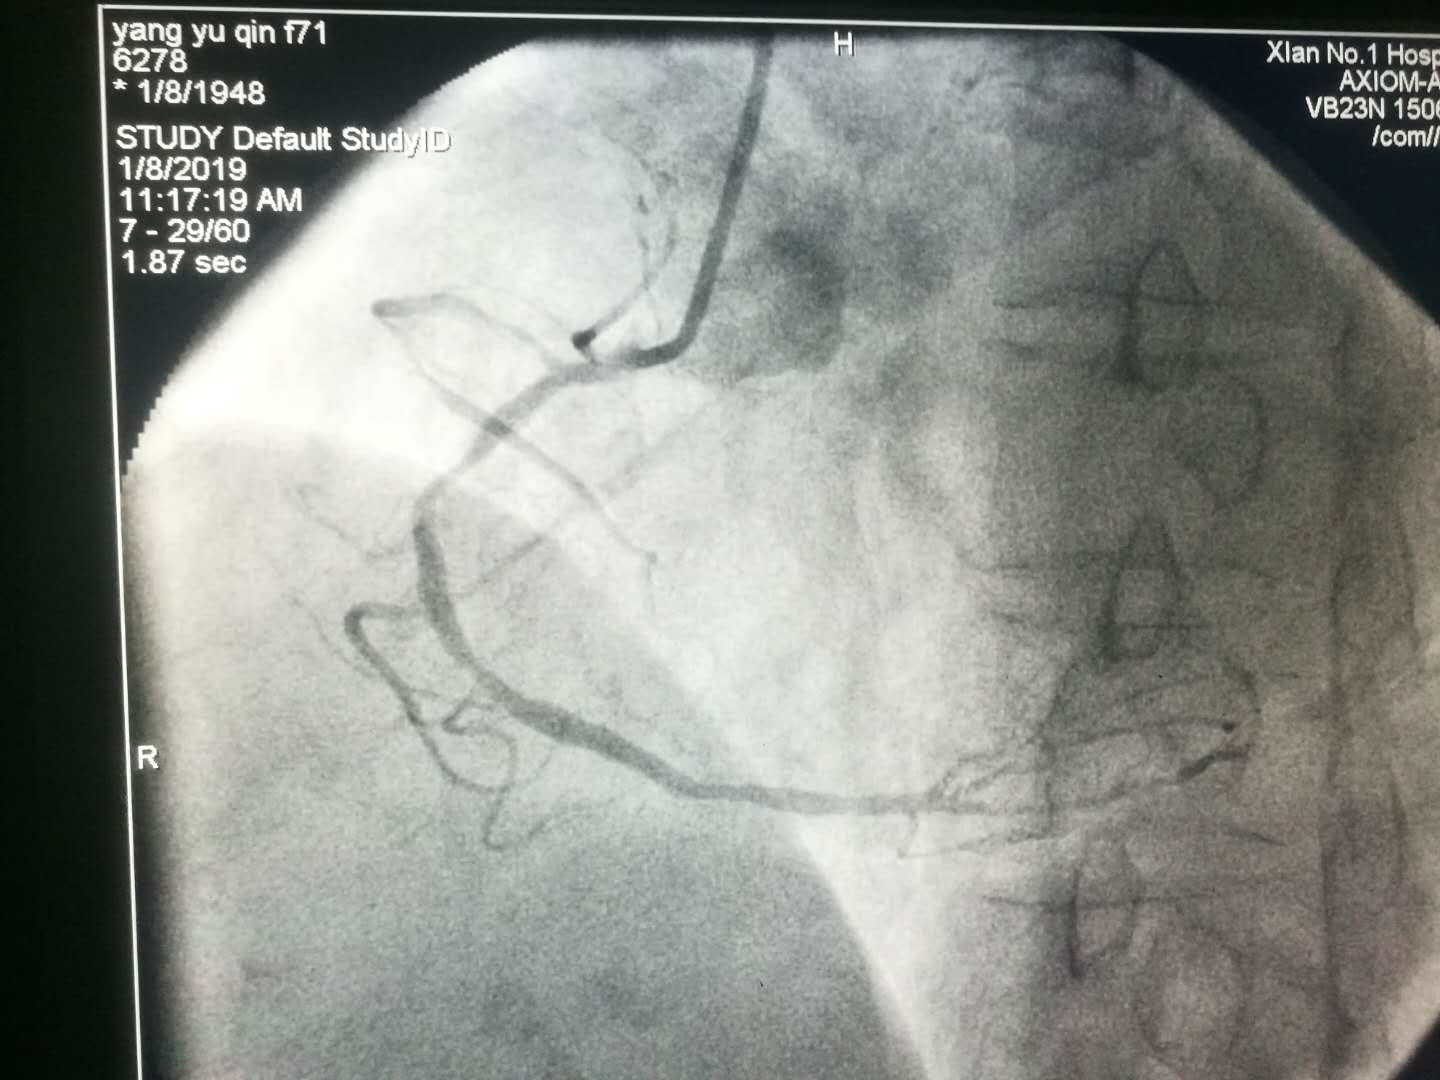

2019新年伊始,文理病区开展了首例冠状动脉造影术及冠状动脉支架植入术。

1月8日上午患者术后在李同华主任的协助下完成文理病区首例冠状动脉造影术加冠状动脉支架植入术。术后患者转入心内四病区监护48小时,1月9日患者平安转回我科继续治疗。整个转诊过程无缝衔接,配合顺畅心血管病医院的各位主任护士长们纷纷表示,只要文理病区需要,术后患者可以转往心血管医院任何一个病区监护。距离无法阻隔我们发展的脚步,无法阻隔我们团结一致为患者服务的信心。